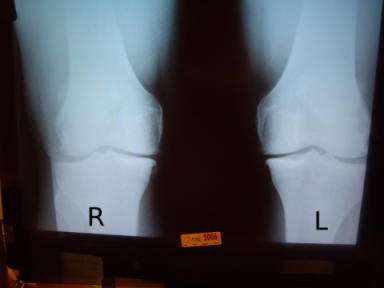

X-rays and Measurements

2006_x-ray

2009_Aug_x-ray

2009_pre-op_x-ray